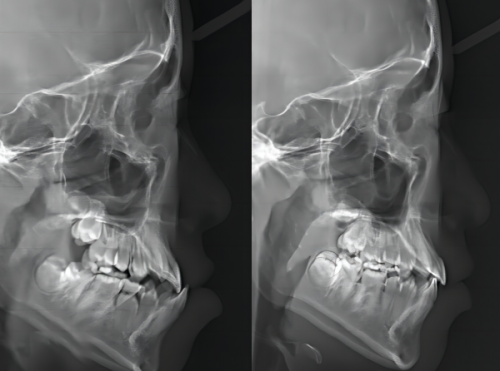

大学生小李牙齿拥挤突出,不敢大笑。李海燕医生为其定制隐适美方案,历时 18 个月,牙齿排列整齐,侧貌线条变得流畅,自信满满地毕业求职。